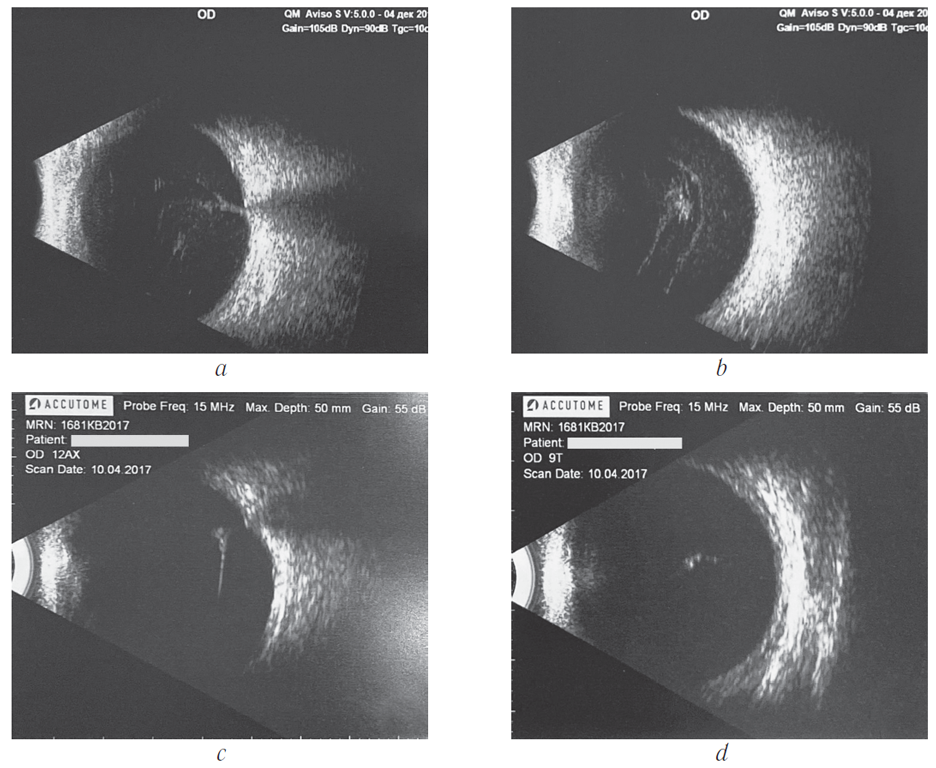

Пациентка И., 55 лет, обратилась по поводу резкого снижения зрения правого глаза в декабре 2016 г. В анамнезе — сахарный диабет 2-го типа на инсулинотерапии. Острота зрения при обращении составила 0,02, коррекции нет. По данным ультразвукового В-сканирования (a, b) диагностирован субтотальный гемофтальм. Через 1 мес. после третьей ежемесячной интравитреальной инъекции ранибизумаба мы наблюдали резорбцию гемофтальма (c, d) с повышением остроты зрения до 0,3, коррекции нет

Patient I., female, 55 years old, presented with a sudden loss of vision of her right eye in December 2016. The patient had a history of insulin-dependent type 2 diabetes mellitus. Visual acuity upon presentation was 0.02, no correction possible. B-scan ultrasound examination (a, b) showed severe vitreous hemorrhage. In 1 month after the third monthly intravitreal ranibizumab injection, a complete resolution of vitreous hemorrhage was found (c, d), accompanied by an improvement of visual acuity up to 0.3, no correction possible